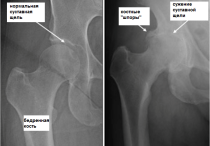

5. Фиксаторы различных видов суставов: коленного, тазобедренного, локтевого.